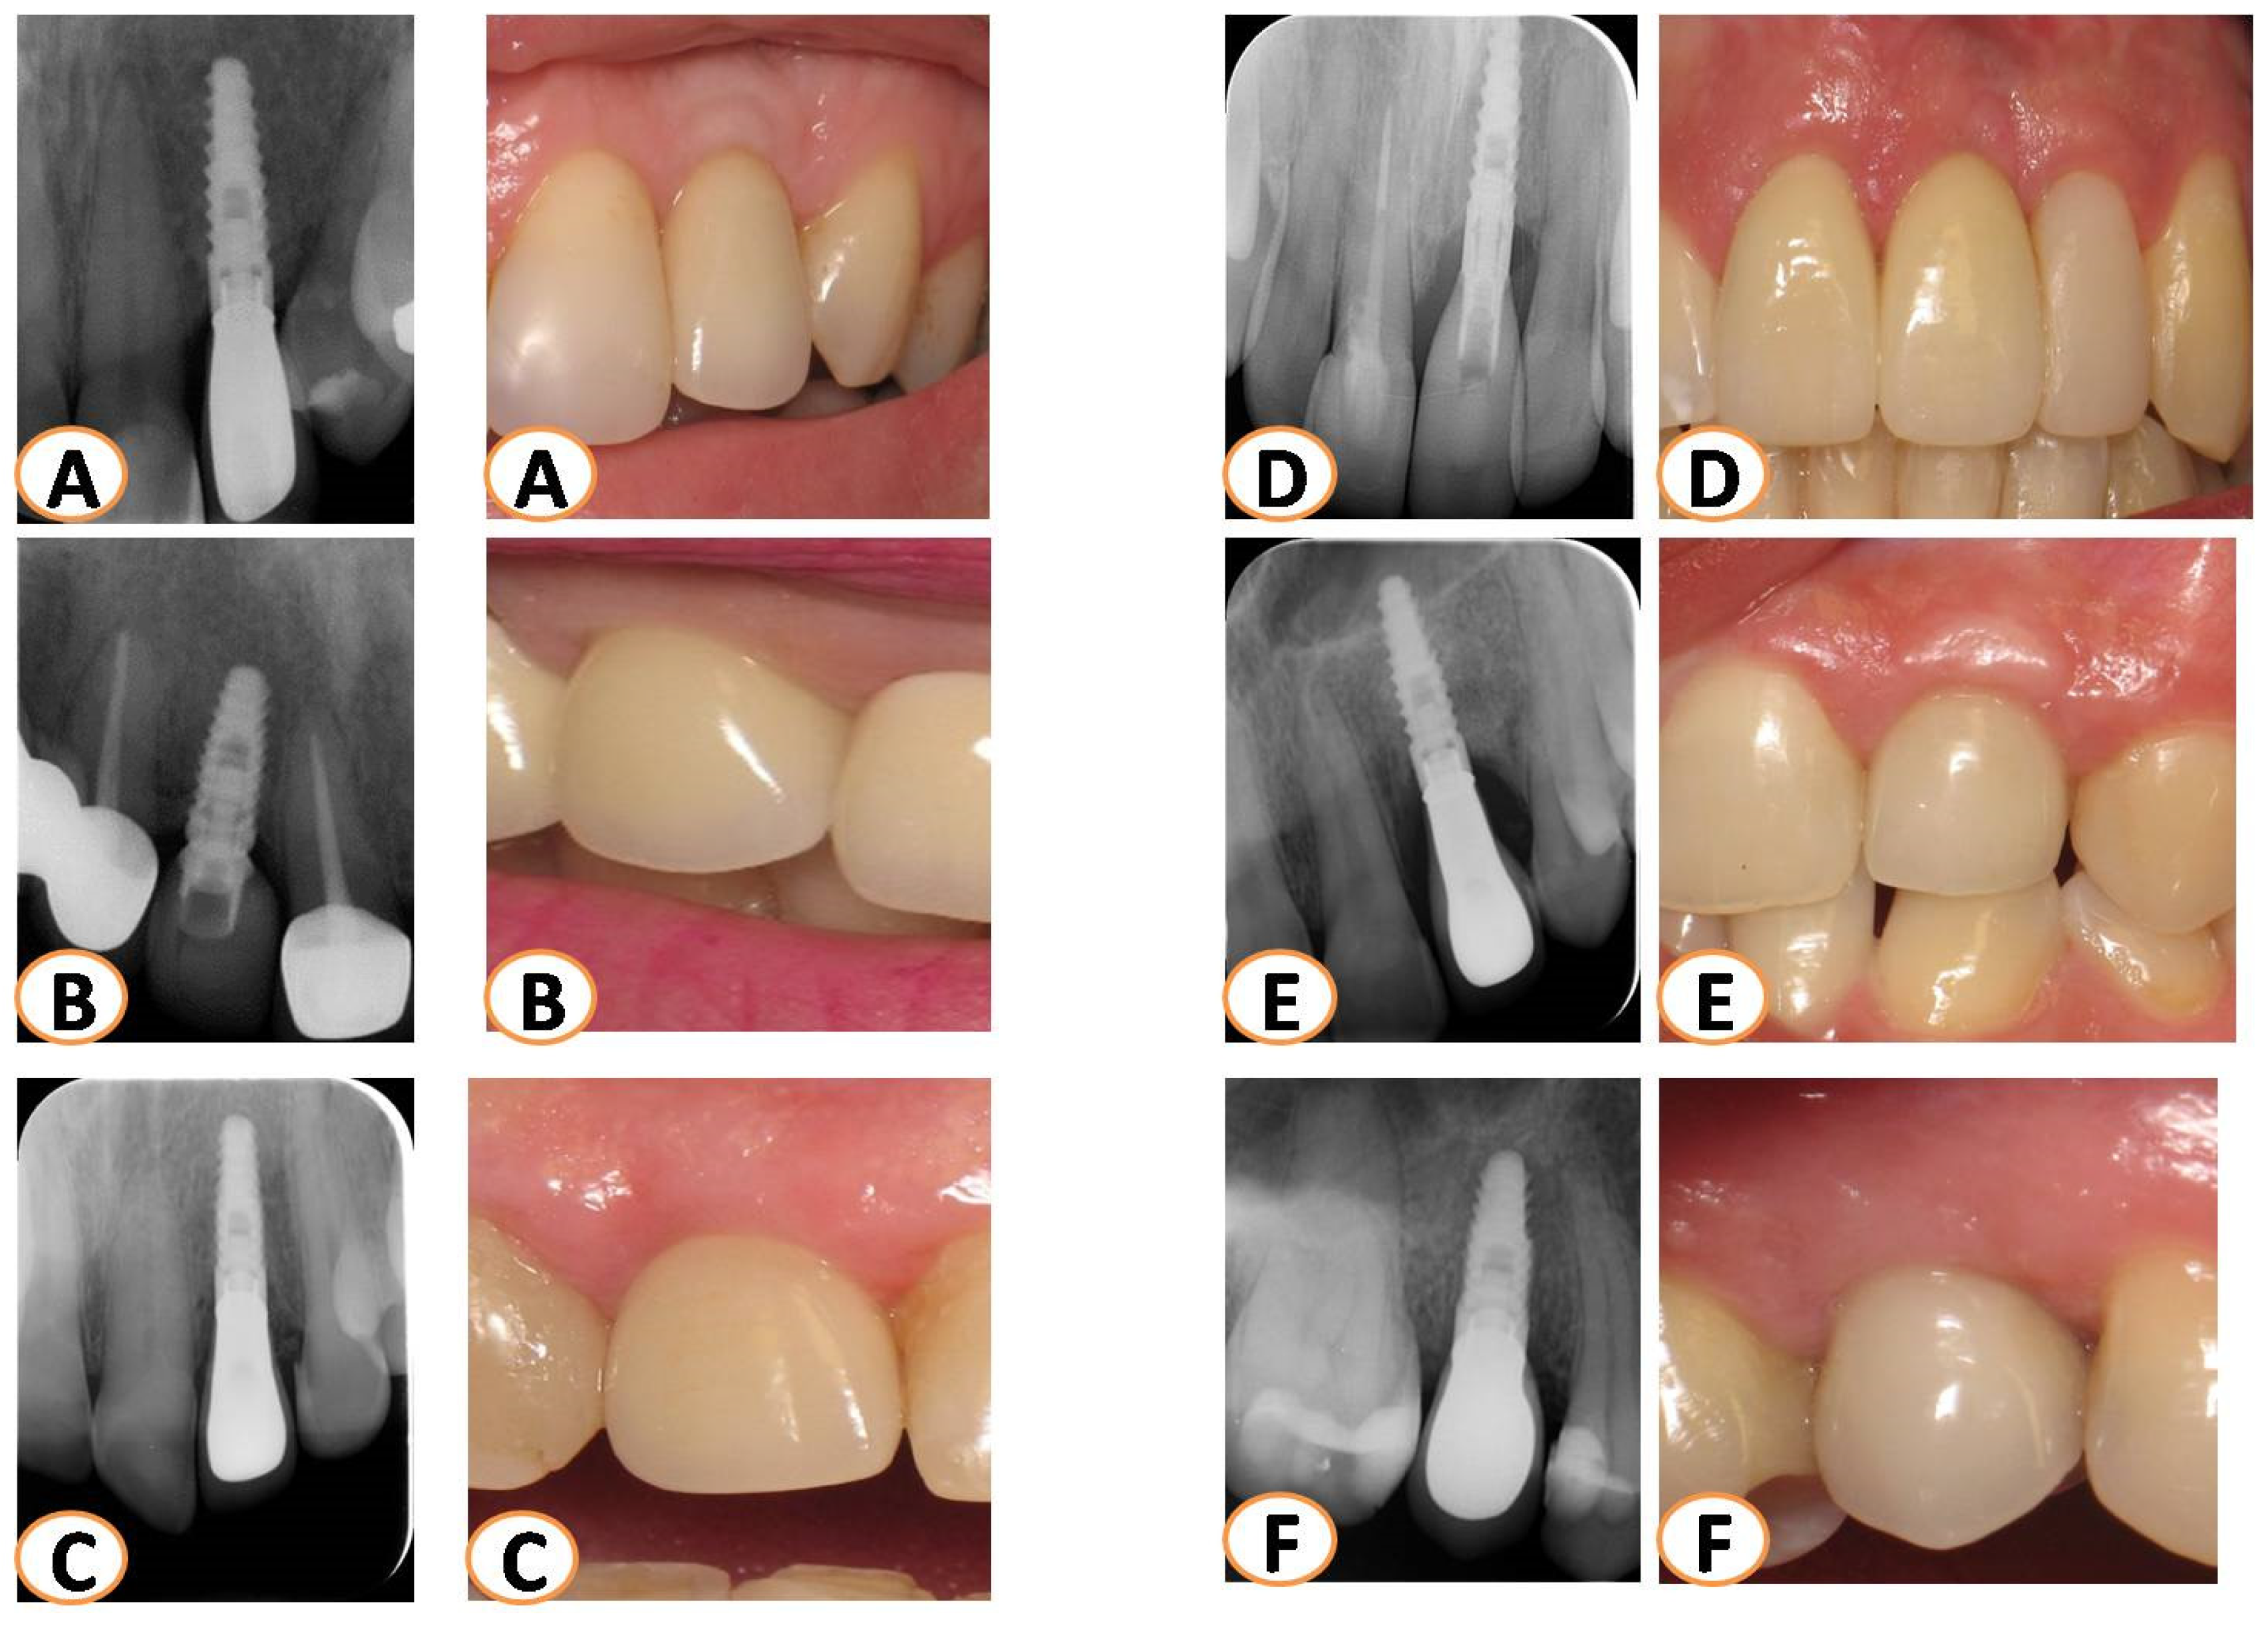

2.4. Long-Term Results of Soft Tissue Esthetic Outcome and Radiographic Evaluation

3.2. PES Assessment